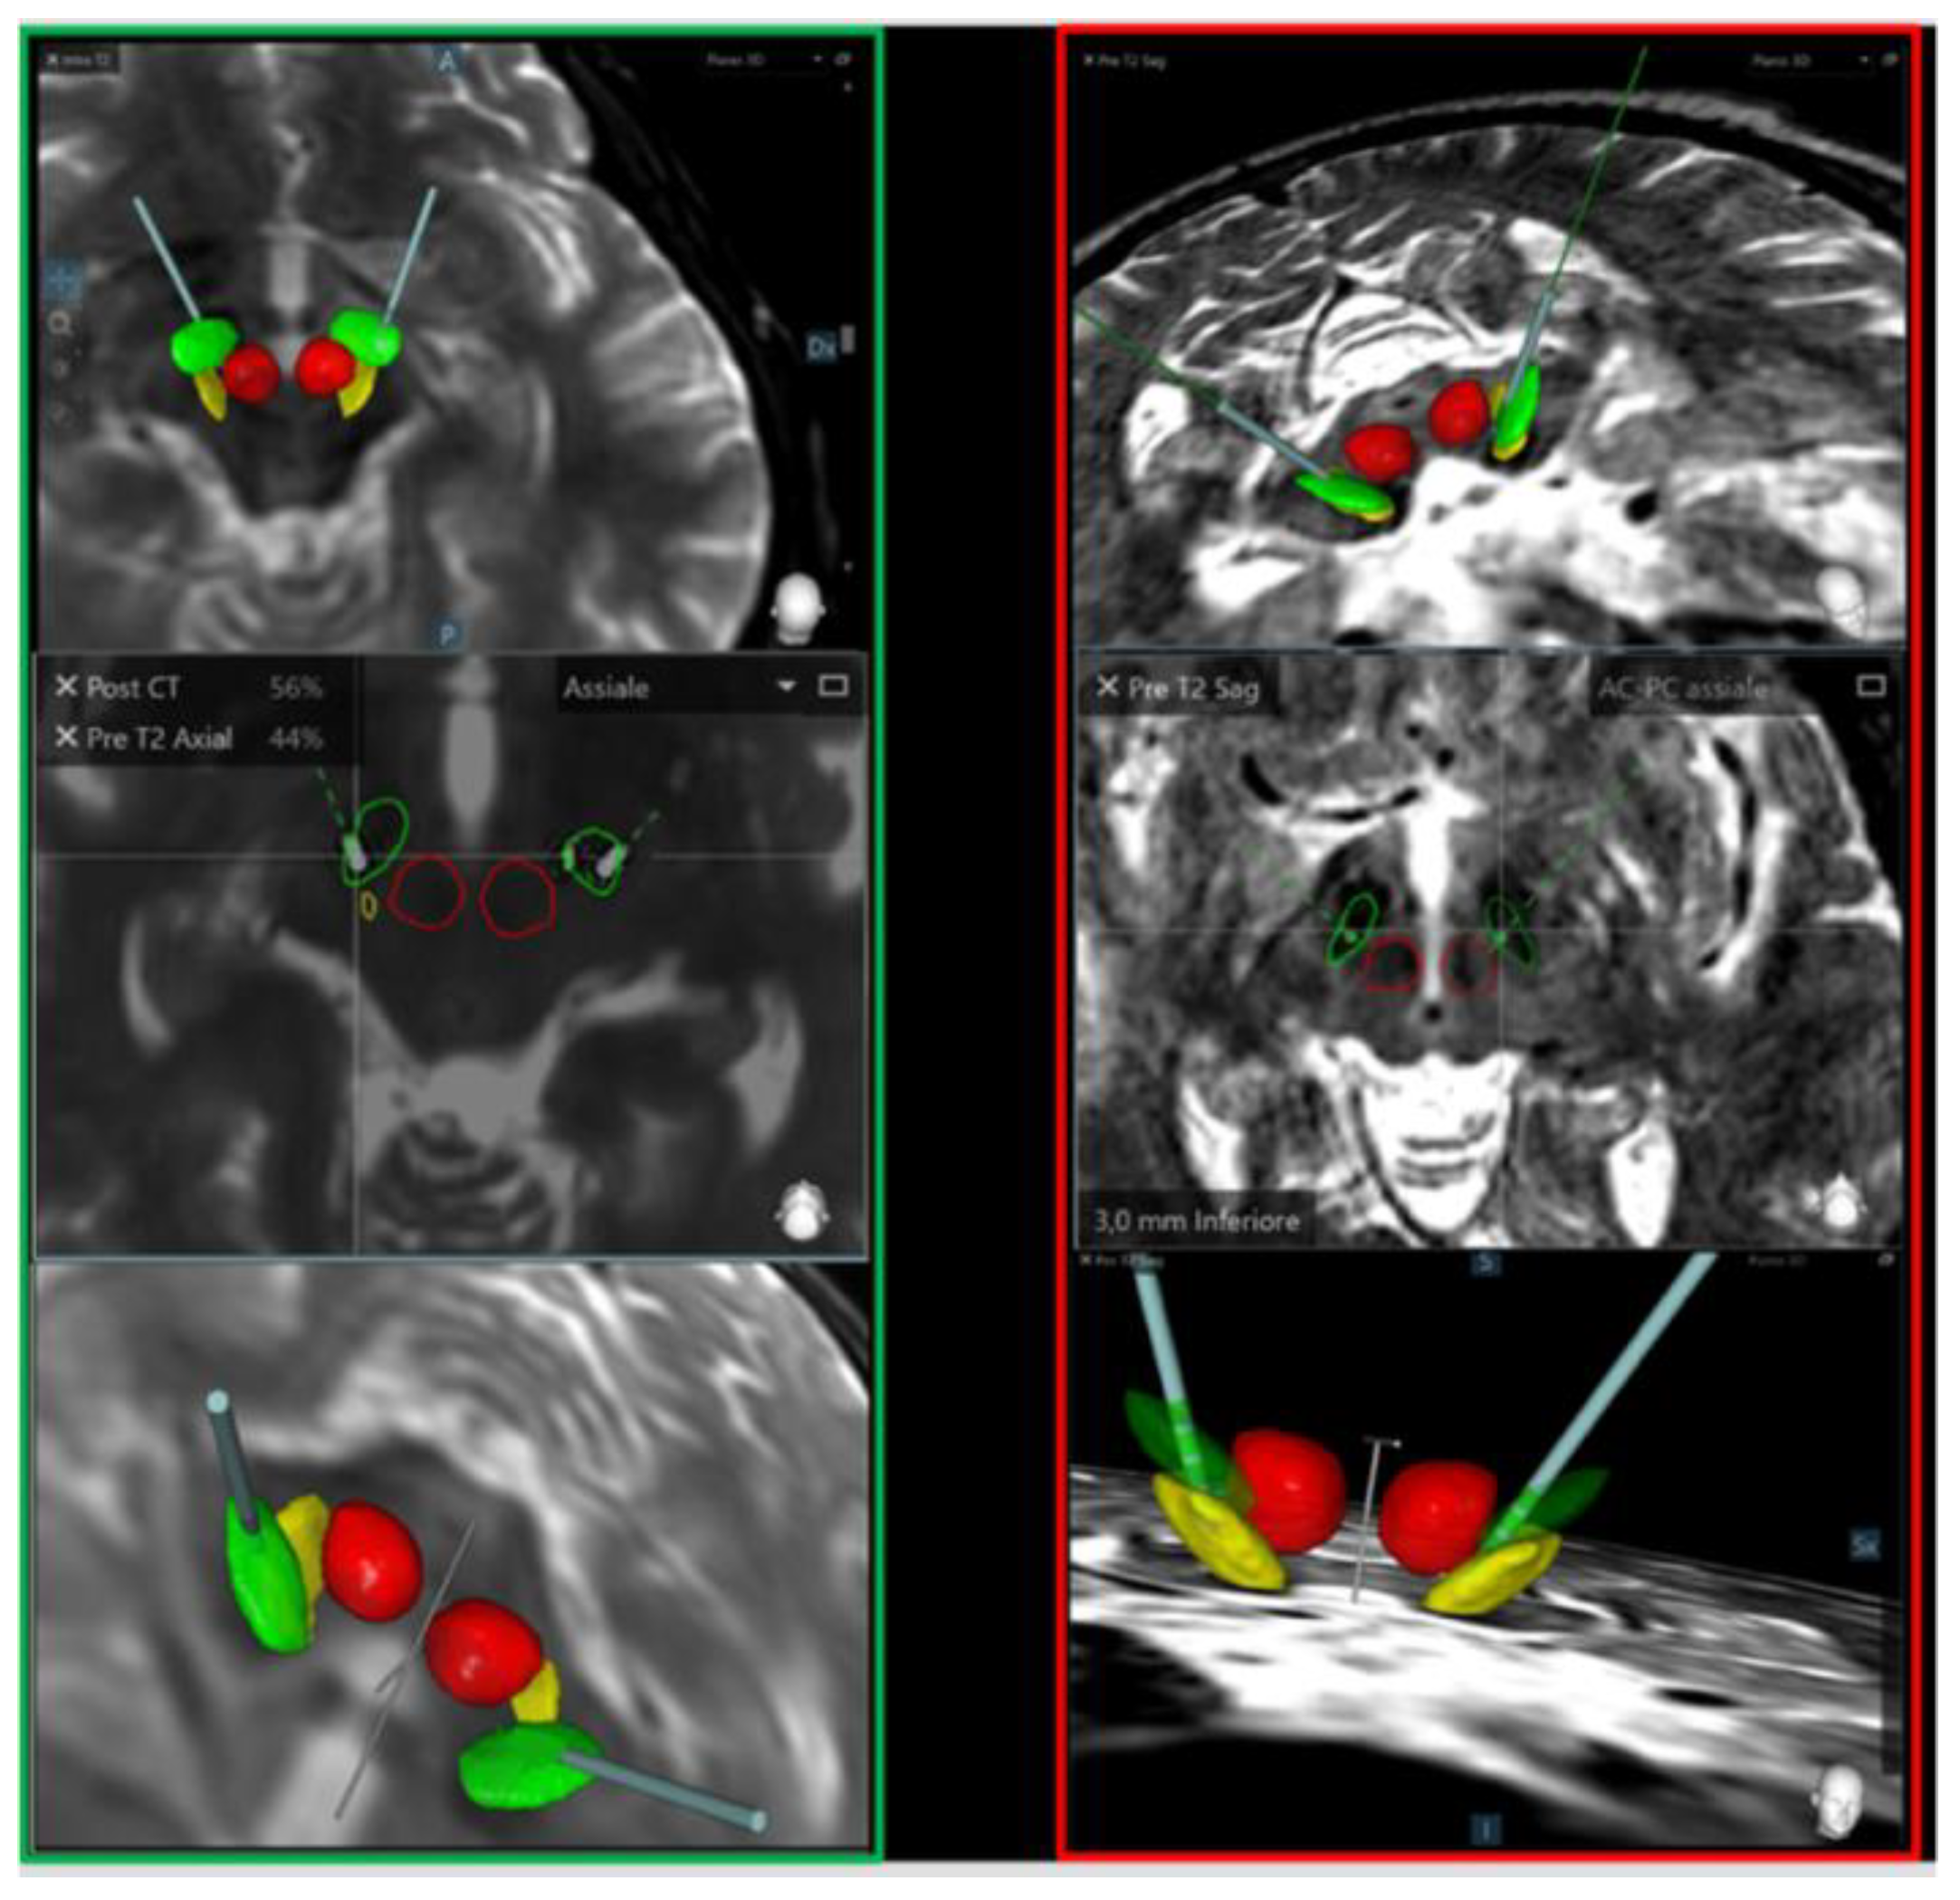

2.5. Imaging